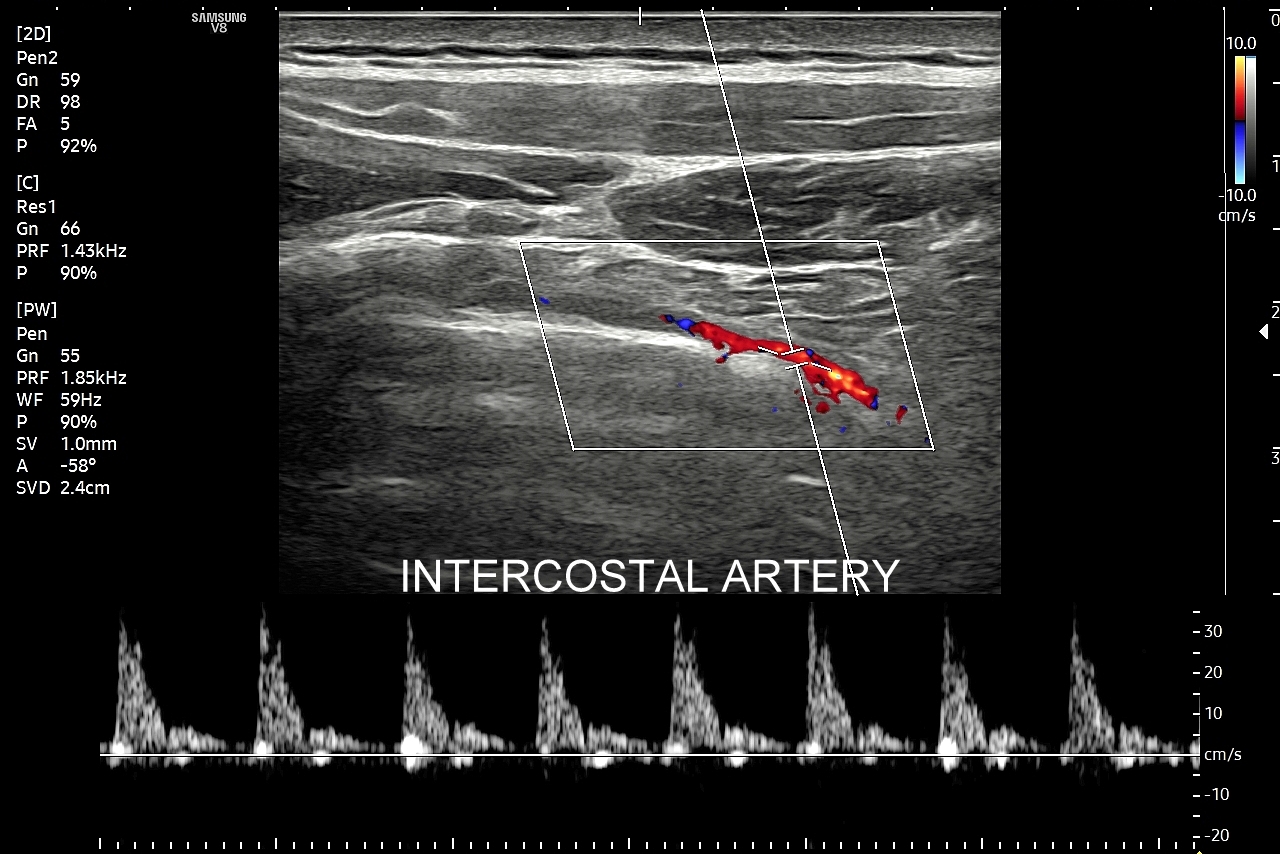

Badanie USG płuc w wybranych przypadkach korzystnie jest połączyć z jednoczesną oceną echokardiograficzną serca oraz dużych naczyń klatki piersiowej, tj. aorty wstępującej i tętnic płucnych. USG układu mięśniowo-szkieletowego klatki piersiowej wykorzystywane jest z kolei w diagnostyce stanów urazowych, takich jak złamanie żeber, czy przeciążenie połączeń chrzęstno-kostnych żeber; w wymienionych przypadkach USG ma wyższą czułość w porównaniu do oceny rentgenowskiej.

Pokrewne badanie USG ścian klatki piersiowej przydatne jest z kolei w diagnostyce stanów urazowych i przeciążeniowych w obrębie układu szkieletowego klatki piersiowej, takich jak złamanie żeber, zespół Tietza, czy naderwanie mięśni. USG klatki piersiowej wykorzystywane jest również przy ocenie zmian guzowatych w powłokach klatki, których przykładami są tłuszczaki, kaszaki, krwiaki, mięsaki i przerzuty nowotworowe.